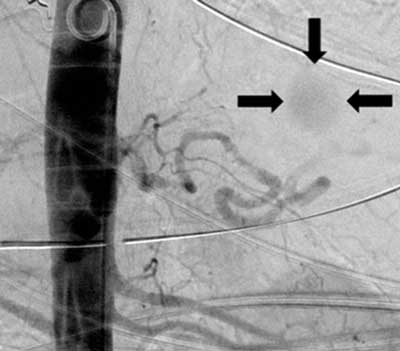

Figure 1

Abdominal aortic angiogram: the 2.5 cm large aneurysm of the distal splenic artery (arrows).